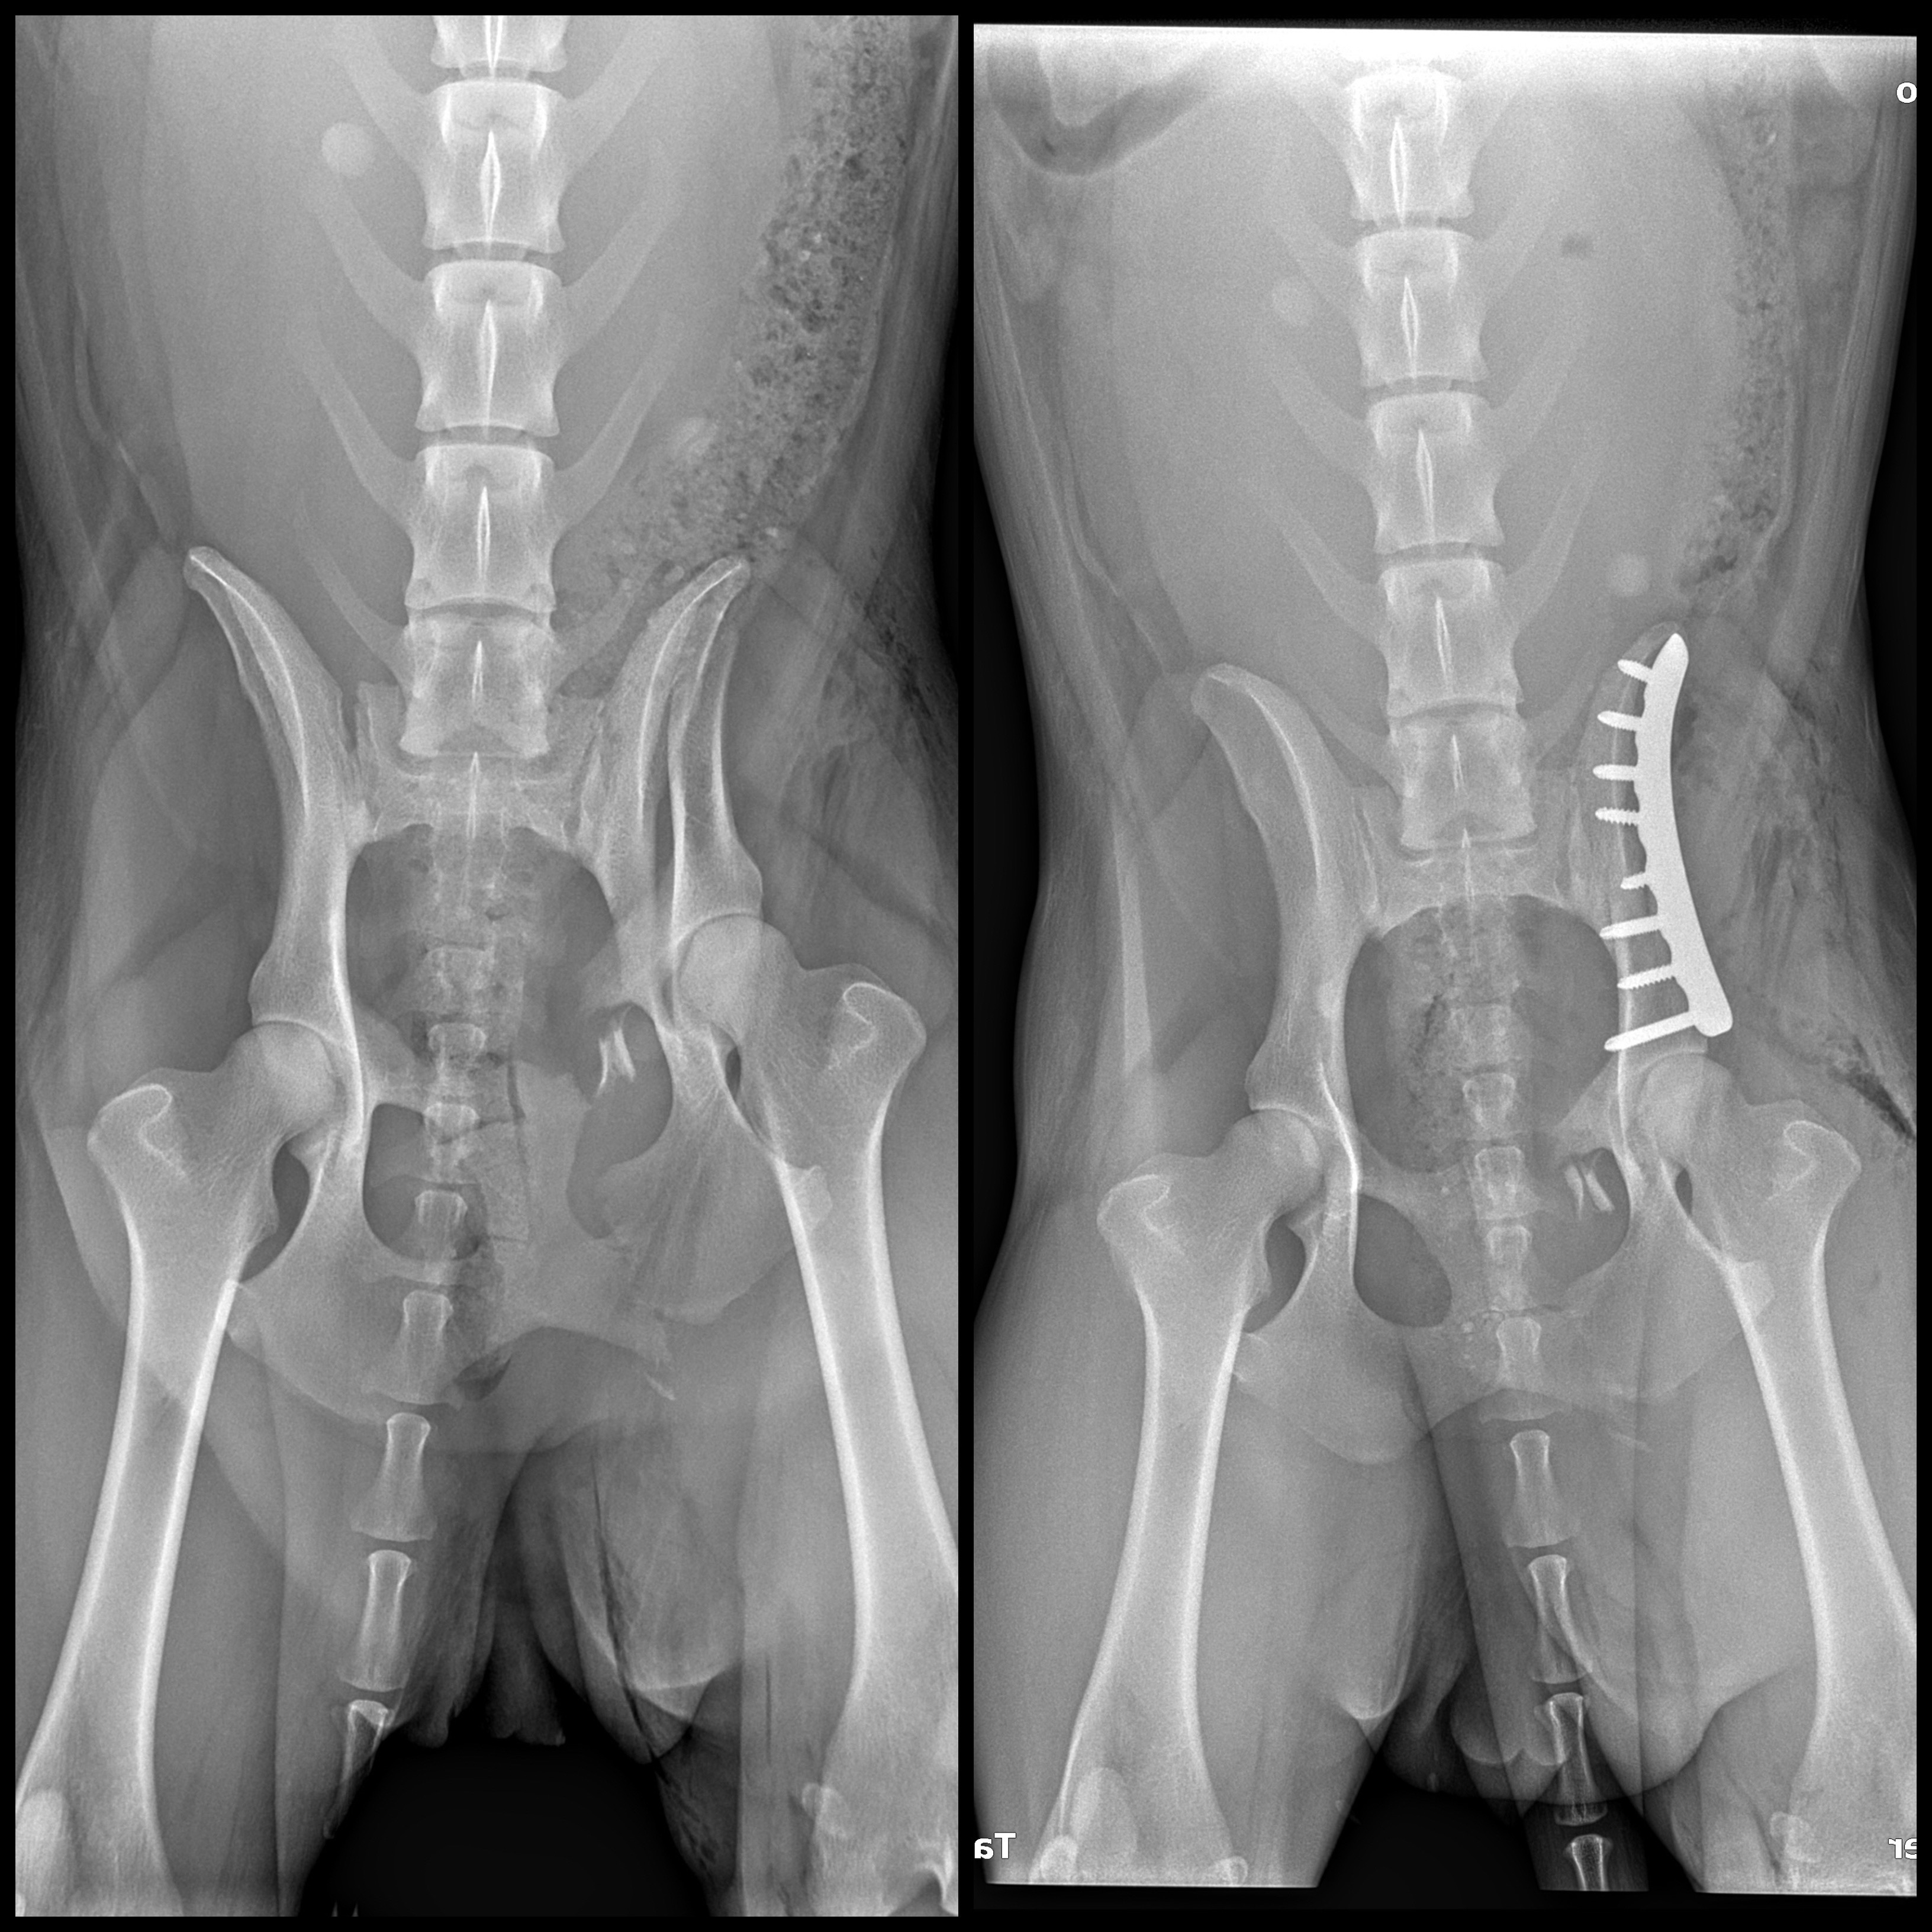

Hi! I am Mako’s partner and protector (well, “owner,” as many would say) Noelle. Last weekend, my adventure companion and working k9 Mako sustained a serious injury while we were recreating in the mountains. This accident (absolutely no fault of little Mako’s) resulted most notably in several fractured pelvic and pubic bones, requiring a plate to be put in, and the rest of the fractures are intended to fuse with rest.

(Pre-surgery fractures on the left, post-surgery xray on right).